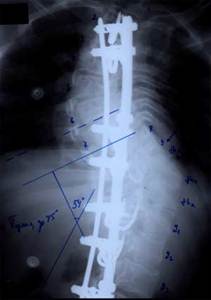

Двухпластинчатый эндокорректор с многоуровневой фиксацией

Нами проведен анализ 209 случаев оперативного лечения сколиотической деформации II - IV степени с использованием двухпластинчатого эндокорректора с многоуровневой фиксацией. Срок наблюдения составил от 1 до 4-5 лет с наличием корректора и от 1 до 3 лет после его удаления. Средний возраст 13,8 года. Врожденный сколиоз был только в 3,83% случаев. Деформация с наименьшим углом по Коббу составила 21°, с наибольшим 124°. Основное число прооперированных больных было с углом искривления в диапазоне 31°-70°. Среди них у 43% угол искривления составил 51°- 60°.

У больных со II степенью деформации коррекция составила 96,56 - 100%

Больной З-ч. 13 лет Сколиотическая деформация II степени грудного отдела позвоночника. Рентгенограмма позвоночника до операции   Результат оперативного лечения. Коррекция 100%

При сколиозе III степени - 88,19 - 91,26%.

Больной П-ко, 15 лет Поясничный сколиоз III степени  Результат оперативного лечения

При сколиозе IV степени с углом деформации в диапазоне от 51° до 70° коррекция составила от 79,2 до 84,8%. С углом от 71° дог 80° - 73,3 - 86,5%. С искривлением от 81° до 122° удалось достигнуть одномоментно коррекции в пределах 72,7 - 73,8%.

Больная Л-ч, 12 лет сколиоз IV степени  Результат оперативного лечения

Коррекция ротационной деформации при II степени сколиоза была 61,83%.

При III степени удалось добиться В среднем коррекции на 59,2%, а при IV степени только на 34,04%. Более низкий процент коррекции сколиотической деформации, как боковой, так и ротационной, объясняется тем, что как правило оперативному лечению с IV степенью подвергаются пациенты с запущенными стадиями заболевания, как правило с законченным ростом, более взрослые, с достаточно уже жестким фиксированным позвоночником. И не менее важно то, что угол деформации большой, часто более 80° - 90°, а это при одномоментной коррекции чревато неврологическими осложнениями различной степени тяжести.